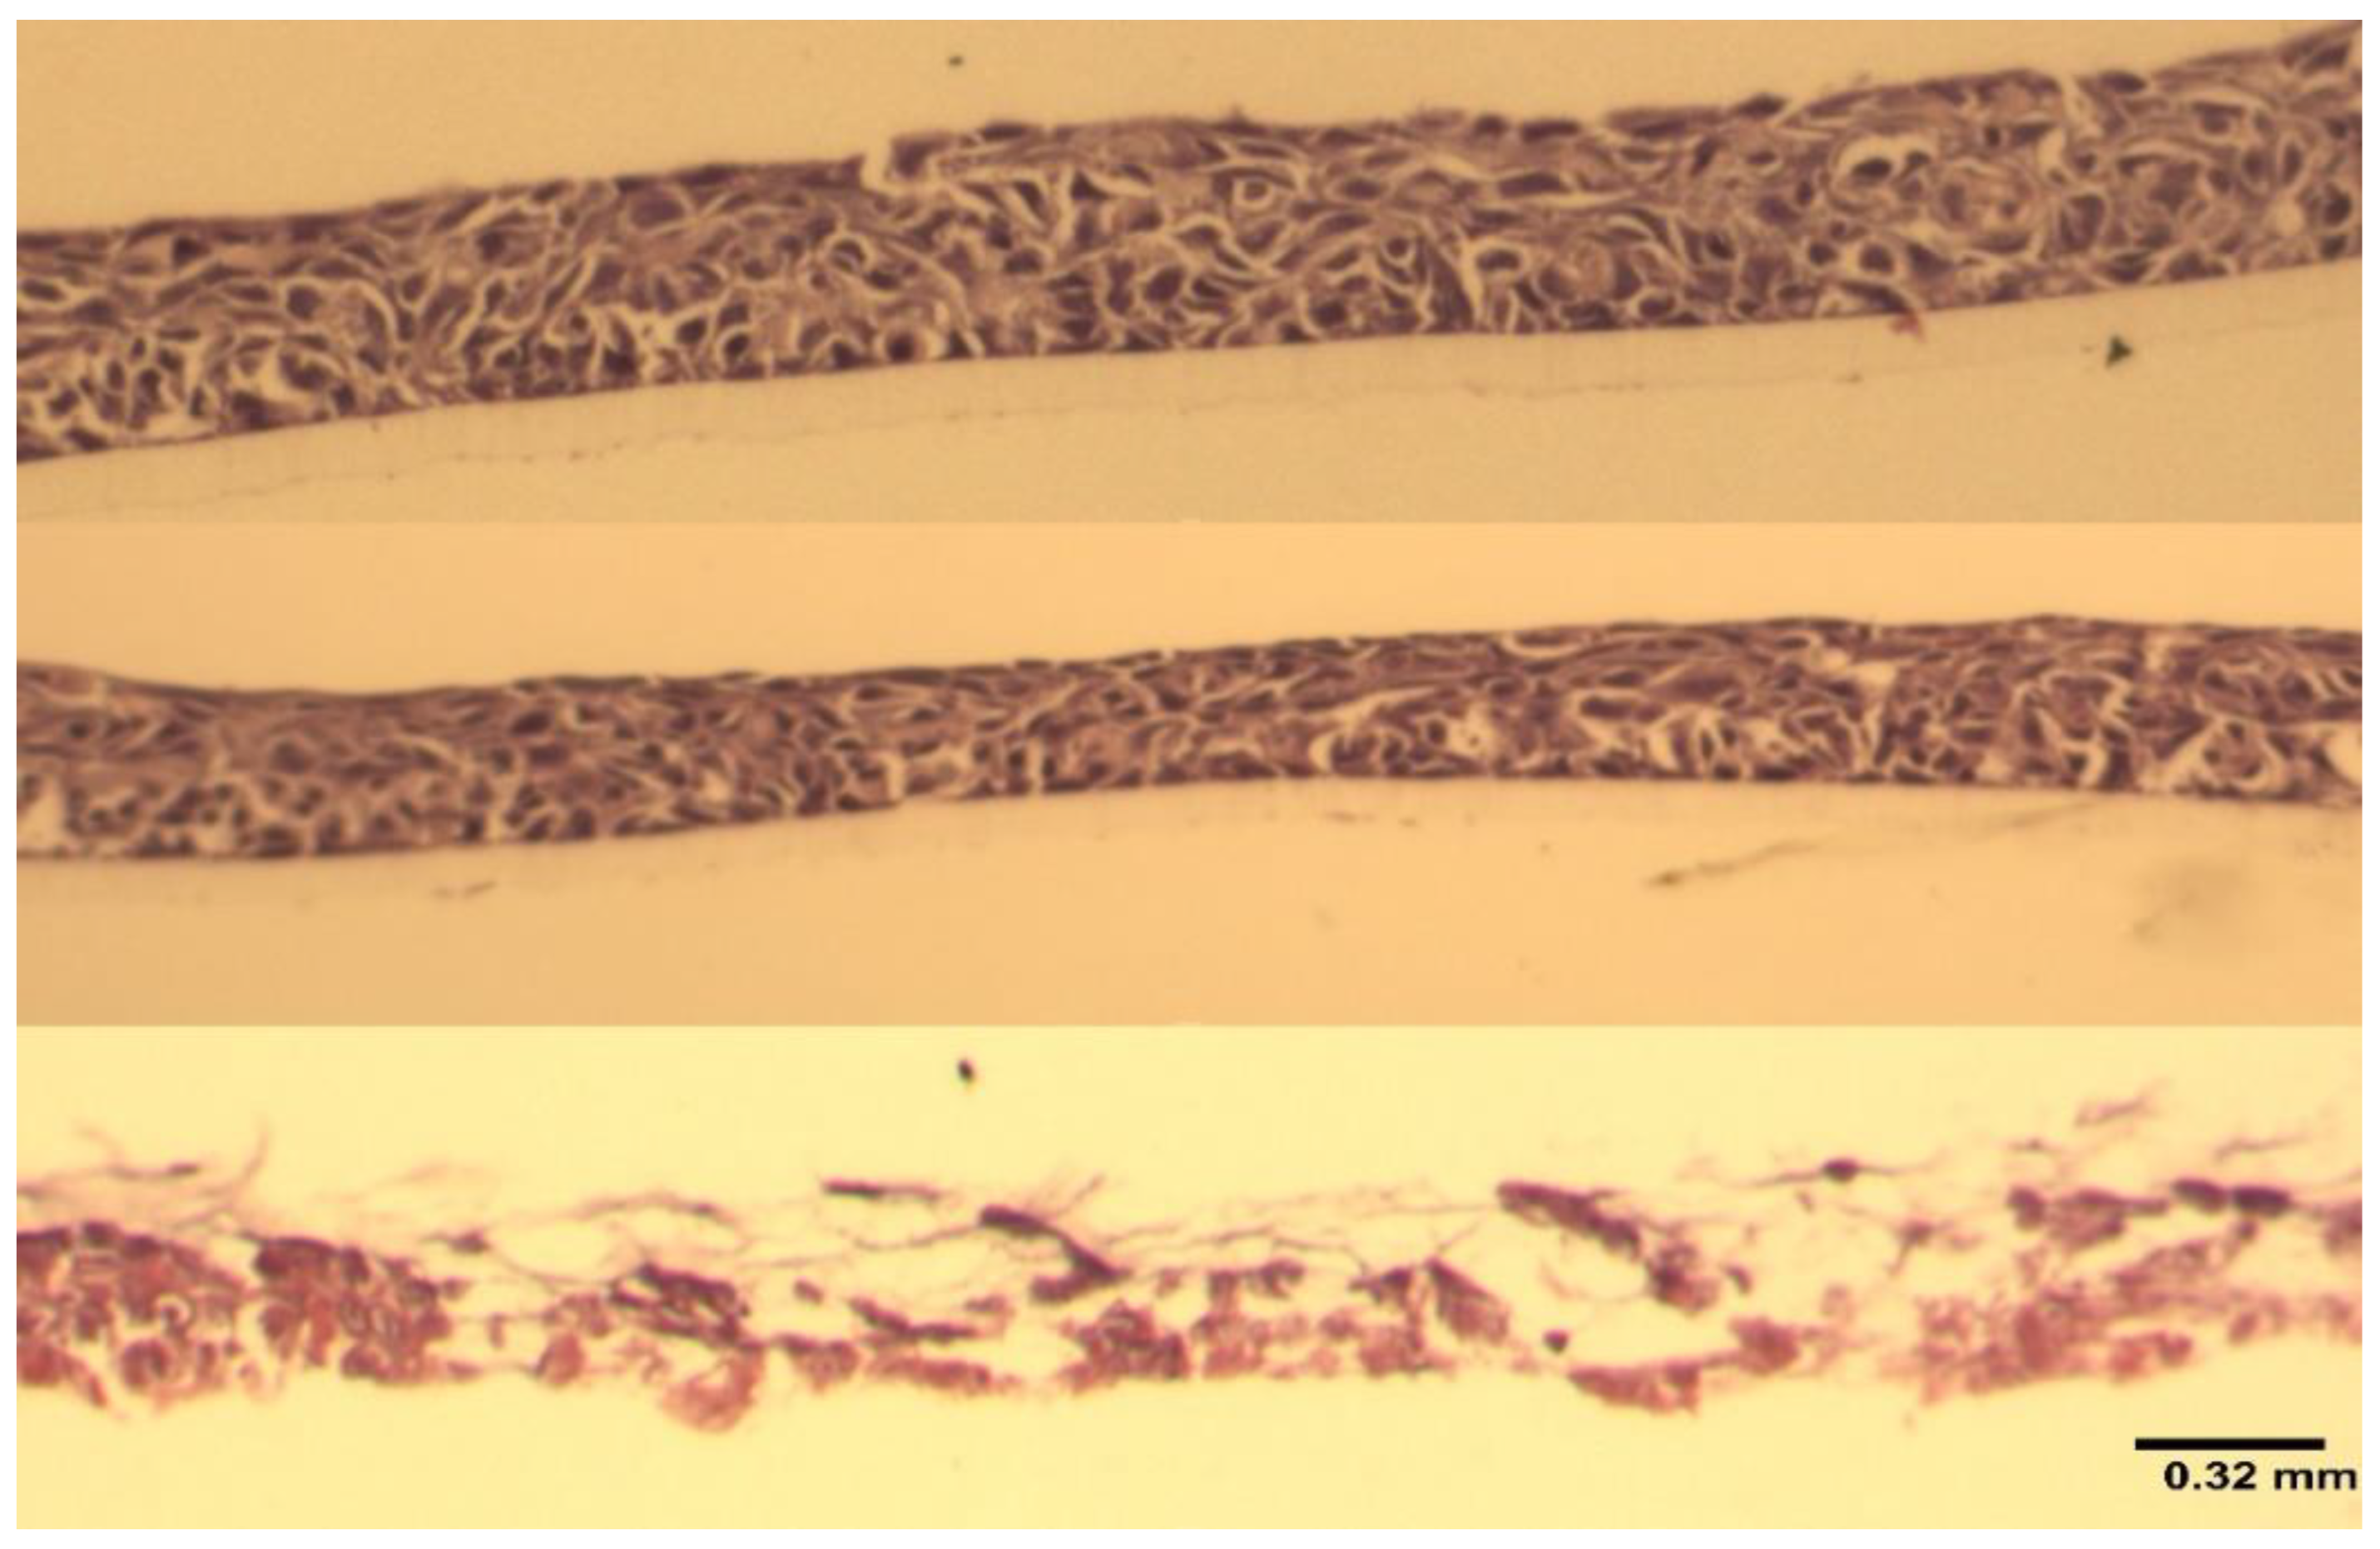

4.5. Histological Examination